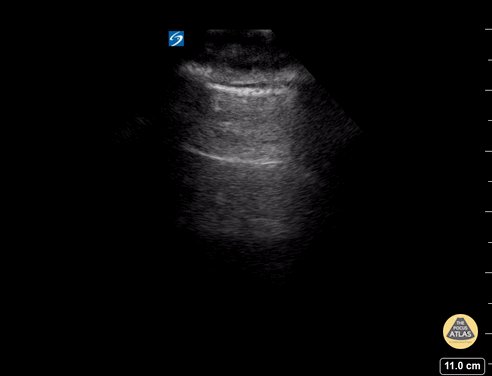

06 - A-lines in lung, normal

07 - Normal pleural / lung sliding